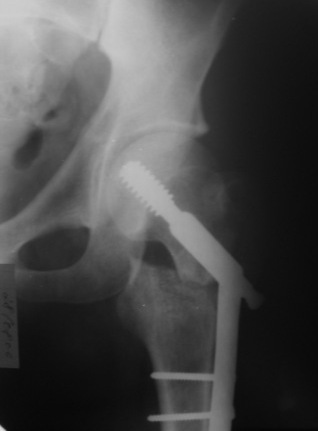

При межвертельных переломах с цефаломедуллярными гвоздями бывает, что проксимальый винт проходит или черед периферический отломок, или прямо над ним. И если остался диастаз, то этот винт при осевой нагрузке не дает сблизиться отломкам. Пример такого остеосинтеза в застарелом случае в приложении.

В качестве предупреждающей меры можно долотом разрушить латеральную стенку дистального отломка под винтом.